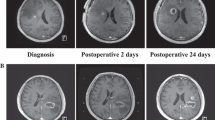

Manual evaluation of contrast-enhancing and FLAIR hyperintensity volume was performed by using the Medical Imaging Interaction Toolkit software (MITK, Workbench and Toolkit 2016.11, provided by the German Cancer Research Center (DKFZ)). MRI data were performed in 1.5 or 3 T scanners. In this multicenter study cohort, MRIs were conducted in the scanners of the respective centers. The tumor volume was outlined on Gadolinium-enhanced T1 MRI data. Measurement of T1-enhancement volume (solid tumor) and FLAIR volume (solid tumor and edema) were performed separately for each patient and time point for volumetric assessment. For the T1-enhancing volume, the inner necrotic zone has been subtracted (solid tumor volume = T1-enhancement volume – volume of necrosis zone). In supplementary Fig. 1A, a3D reconstruction example of tumor segmentation is shown. The tumor volume, that is defined as “region of interest” (ROI) is shown in red.

ADC analysis

All imaging data were co-registered performed using the “multimodal.rigid.default” registration algorithm in the Medical Imaging Interaction Toolkit [25]. Subsequently, the combined ROI of FLAIR and T1-enhancement volume was used to determine the mean ADC value from both baseline and progression time point in the tumor region (Supplementary Fig. 1B). For comparison between treatment groups, the absolute change of Mean ADC-value from baseline to progression time point was compared between patients with short PPS and long PPS.

Seventy patients (about 80% of the patients that were included in the survival analysis in this study) were evaluable for imaging analysis and constituted the cohort on which all following MRI analyses are based on. Patients with long PPS in the CCNU/TMZ arm showed a tendency to a stronger increase in T1-enhancement volume (mean delta 4.600,1 mm3 vs. 1.747,9 mm3, p = 0.219, Fig. 3A) but not in FLAIR volume (mean delta 19.749,9 mm3 vs 13.690,8 mm3, p = 0.682, Fig. 3B) at progression as compared to long PPS patients of the TMZ arm. Overall, in the TMZ monotherapy arm, patients with short PPS could be well distinguished from patients with long PPS by their strongly increasing volumes of contrast-enhancement (mean delta 8.055,7 mm3 vs 1.747,9 mm3, p = 0.005) and FLAIR hyperintense lesions (mean delta 31.689,9 mm3 vs 13.690,9 mm3, p = 0.03). In contrast, patients with CCNU/TMZ combination therapy showed no difference in T1-enhancement increase (mean delta 7.227,5 mm3 vs 4.600,1 mm3, p = 0.567) or FLAIR increase (mean delta 25.356,7 mm3 vs. 19.7489,9 mm3, p = 0.914) in short-PPS vs. long-PPS patients. In summary, in the TMZ monotherapy arm, the increase of the contrast-enhancing lesion and FLAIR lesion at mRANO-defined progression was inversely related to OS, whereas in the CCNU/TMZ arm, no such relation was observed. Thus, these parameters do not allow to distinguish patients with long PPS from patients with short PPS in the CCNU/TMZ group at mRANO-defined progression time point.

Analysis of ADC maps revealed no statistical difference of mean ADC values between treatment groups as a whole at baseline time point (Fig. 4A). However, long PPS patients of the CCNU/TMZ group showed a higher absolute increase in ADC value from baseline (last prior to progression) to mRANO progression time point than long PPS patients of the TMZ group (Fig. 4B, p = 0.017). These data suggest that CCNU/TMZ therapy might lead to changes in tumor structure that can be identified in ADC imaging and may be different from the radiological changes seen in patients after TMZ monotherapy.

ADC analysis of T1-enhancement region of interest (ROI). For each patient in each group Mean ADC value of T1-enhancing tumor ROI was calculated. In (A) the Mean ADC value of baseline tumor (last prior to progression) is shown. There is no significant difference between long PPS TMZ arm and long PPS CCNU/TMZ arm (p = 0.94, Mann–Whitney test). In (B) the absolute change in Mean ADC value of T1-enhancement ROI from baseline to progression time point is shown. The change is significantly higher in long PPS CCNU/TMZ arm, comparing to long PPS TMZ arm (p = 0.017, Mann–Whitney test). Error bars show 95% confidence interval of Means. Statistical analysis was performed using Mann–Whitney-test. p < 0.05 was considered significant and marked as * = < 0.05